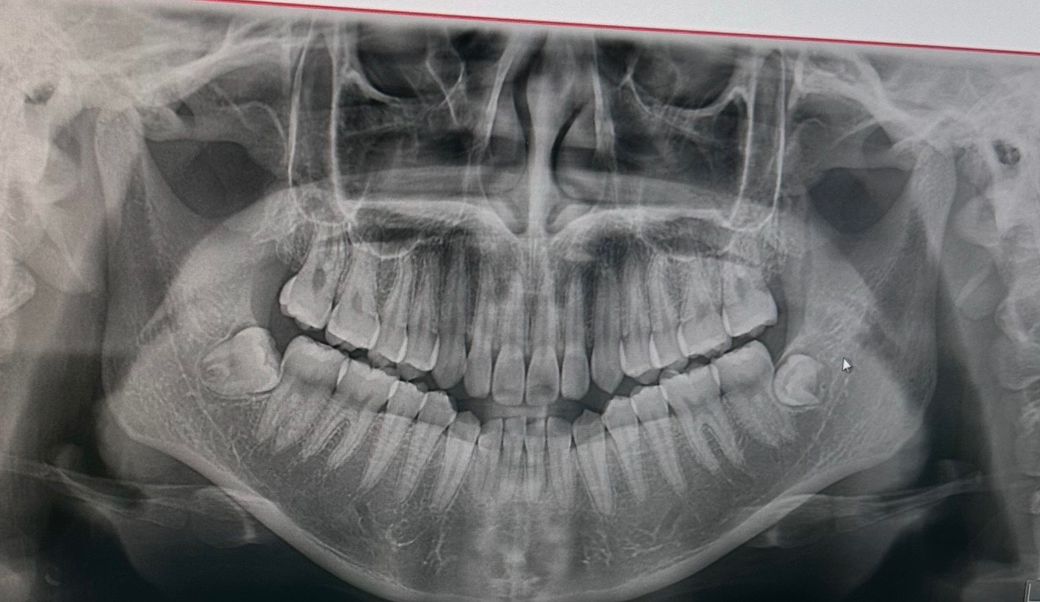

턱관절 과두 갈린건가요? 뭐가 문제인지 모르겠어요

근육문제라고는 하는데 제가보기에는 계속 무턱되고 있는중이고 오픈바이트도 생긴것같아요 정말 과두 갈린거 아니고 아무문제없고 근육만 큰가요?? 뭐가 문제인지 알려주세요...ㅠㅠㅠ이갈이가있어서 스플린트도 끼고있어요

그리고 궁금한게 하나있는데 첫번째스진에서는 왜 치열이 둥글게 u자형이고 두번째에서는 일직선으로 되어있는건가요?? 각도차이인가요

파노라마 찍을 때 위치 잡을 때 턱을 숙이고 찍으면 U 자로 나오고 턱을 들고 찍으면 편평하게 옆으로 퍼저 나옵니다.

치열이 달라보이는 것은 단순한 각도차이 이며 턱관절은 해당 엑스레이가 아닌 턱관절 엑스레이로 확인해야합니다.

치열 사진이 다르게 보이는 것은 방사선 조사각의 차이입니다. 즉 방사선을 어떻게 조사했는지에 따라 펴져 보일 수도 있고 v자형처럼 보일 수 있습니다. 이러한 조사각에는 촬영 당시의 환자 분의 머리 위치 및 자세에 영향을 받습니다.

지금 사진에서는 과두와 관절원판과의 관계를 파악하는데 한계가 있습니다. 관절 부위를 정확히 파악할 수 있는 다른 x-ray 촬영이나 ct 촬영을 하셔야 정확한 판단이 가능합니다.

턱관절이 안좋으면 대학병원 구강내과를 가셔서 턱관절 검진을 받아보시고 치료를 받으시는게 좋을것같습니다. 엑스레이 사진은 찍을때 고개를 더 들거나 숙이면 저렇게 차이가 날수 있습니다.

위 사진상에서는 아주 심각한 턱관절 마모 등의 양상은 보이진 않습니다. 두 사진에서의 차이점은 고개를 얼마나 숙였냐의 차이일 것 같습니다.